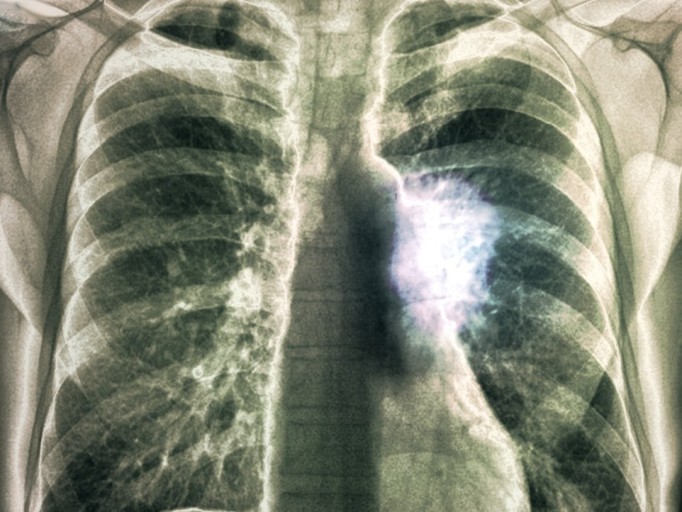

- 정기적인 건강 검진: 위와 같은 증상이 하나라도 나타나면 즉시 병원을 방문하여 흉부 X-ray, CT 촬영 등 검사를 받는 것이 중요합니다.